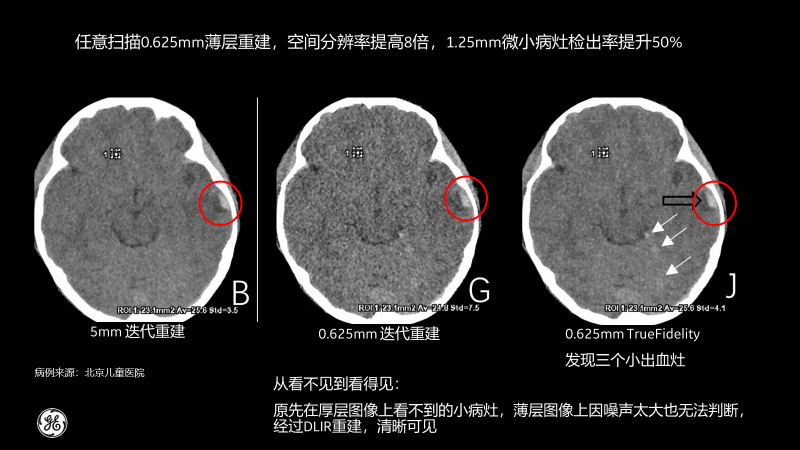

相比傳統(tǒng)CT圖像對腹部檢查一般都選擇5mm厚層重建,TrueFidelity可對任意體型任意部位的檢查進(jìn)行0.625mm的薄層圖像重建,真實(shí)還原圖像的解剖細(xì)節(jié)和紋理,提高微小病灶的發(fā)現(xiàn)幾率,有助于早診早治,極大提高醫(yī)生的診斷信心。

北京兒童醫(yī)院的測試病例也顯示,經(jīng)過TrueFidelity,任意掃描0.625mm薄層重建,空間分辨率能提高8倍,1.25mm微小病灶檢出率提升50%,最終額外發(fā)現(xiàn)了3個之前看不到的微小病灶。